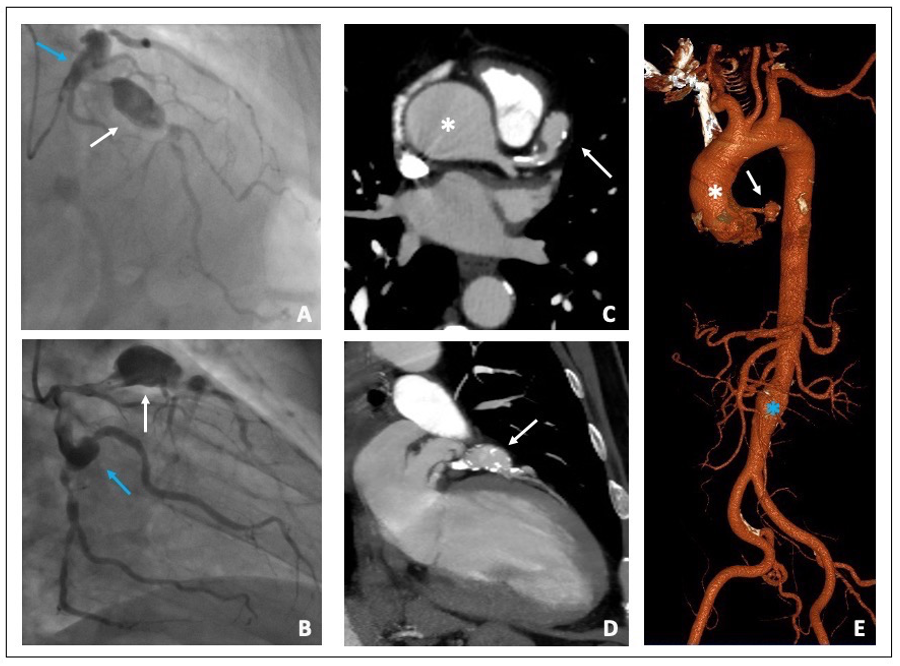

The coronary angiography showed two “in tandem” giant and saccular aneurysms in the proximal and middle left anterior descending artery and another aneurysm in the proximal Circumflex artery. Both LAD and Circumflex artery had a critical stenosis distally to the aneurysms; finally, a right coronary artery chronic total occlusion was shown. (Figure 2A,B).

Figure 2. (A,B) Coronary angiography. (A) Proximal LAD giant aneurysm (white arrow) followed by a severe stenosis. Proximal left circumflex artery ectasia (blue arrow). (B) Proximal left circumflex artery ectasia (blue arrow) followed by a severe stenosis of the distal segment. Proximal LAD giant aneurysm (white arrow) (C,D) MSCTA Cardiac short and long axis view showing both ascending aorta (white asterisk) and LAD aneurysms (white arrow). (E) 3D aortic reconstruction image: Ascending (white asterisk) and infra-renal aortic aneurysms (blue asterisk) and LAD aneurysm (white arrow). LAD (left anterior descending); MSCTA (multi-slice computed tomography angiography).

The thoraco-abdominal MSCTA showed an ascending aortic aneurysm of 48 mm in transversal diameter and a fusiform aneurism of the infra-renal abdominal aorta 30 mm in diameter, with a thrombotic apposition to the aneurysm wall. MSCTA confirmed the presence of a giant aneurysm of the proximal left anterior descending coronary artery that was 20 mm in diameter with a modest thrombotic stratification (Figure 2C–E). The heart team established surgical treatment to be the best treatment option for this patient. A combined coronary artery bypass grafting, surgical exclusion of the coronary aneurysms and ascending aorta replacement with a vascular prothesis was performed without any complications at discharge and at one-month follow-up.